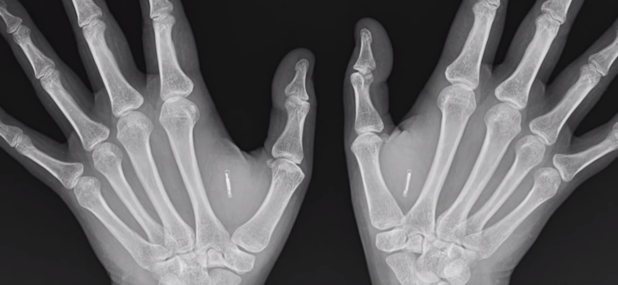

Digital certificates are convenient for a number of reasons, like being able to be handled by a microchip that could be conveniently injected under the skin so that people never forget to carry them around everywhere they go.